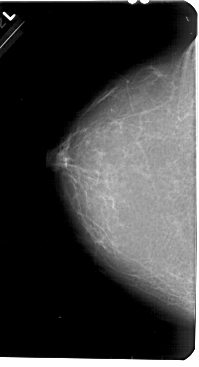

A_1680_1.RIGHT_MLO

RIGHT_MLO LINES 5491 PIXELS_PER_LINE 3091 BITS_PER_PIXEL 12 RESOLUTION 43.5 OVERLAY

FILE: A_1680_1.RIGHT_MLO.OVERLAY

TOTAL_ABNORMALITIES 1

ABNORMALITY 1

LESION_TYPE MASS SHAPE ROUND MARGINS CIRCUMSCRIBED

ASSESSMENT 3

SUBTLETY 3

PATHOLOGY BENIGN